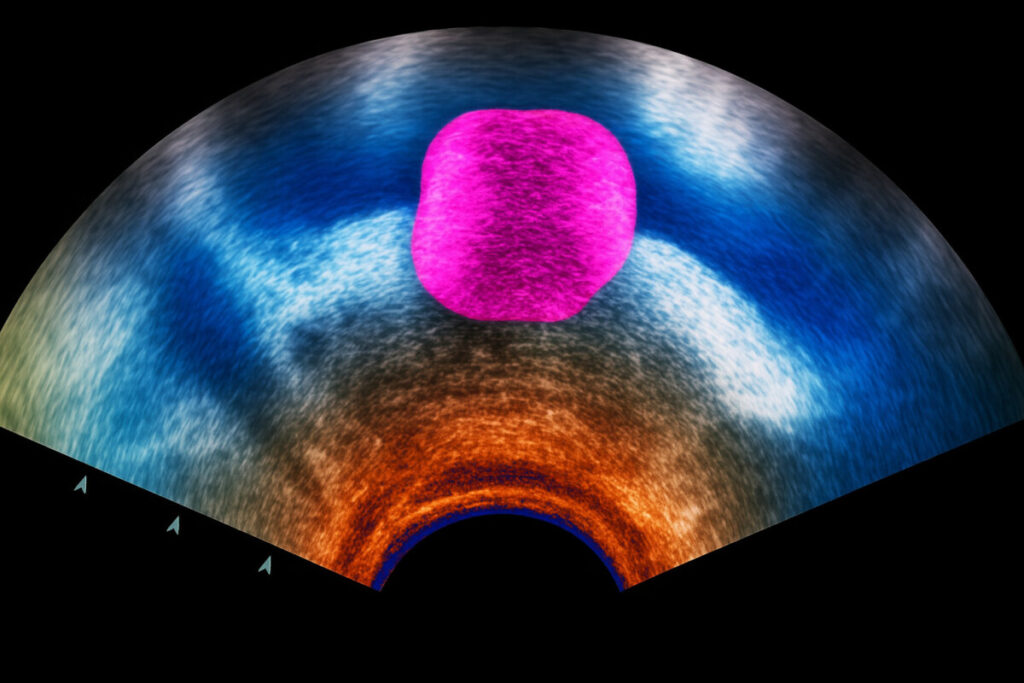

다만, 전립선염 등도 PSA 수치를 증가시킬 수 있습니다. 혈액 검사, 초음파, 조직 검사 등의 추가 검사를 통해 원인을 정확히 구별할 수 있습니다.